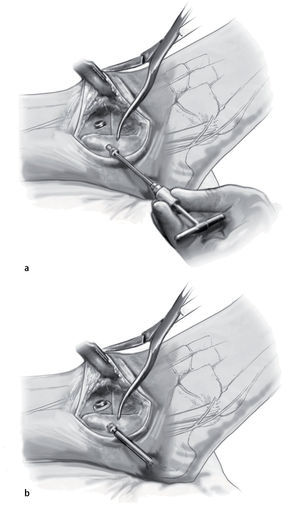

Fig. 6 Realice la osteotomía en la tibial distal perpendicular al eje tibial. Cuando se realiza de medial a lateral, el paquete neurovascular posteromedial es visible y se puede supervisar. La resección de la tibia debe ser lo menor posible para evitar el acortamiento de la extremidad.

Fig. 7 Coloque el pie en la posición deseada usando el lado contralateral como plantilla. Plantígrado con 5-8º valgo y 5-15º de rotación externa. Cuando se haya identificado la posición deseada, se realiza una osteotomía sutil de la superficie superior del astrágalo de forma exactamente paralela a la osteotomía tibial.

Fig. 8 Compruebe la alineación apretando a la vez los cortes del astrágalo y de la tibia. Debe cuidarse la alineación neutra del retropié para que la altura sea idéntica en todas las direcciones.

Fig. 9 Compruebe la alineación y aplique fijación provisionalmente con el uso de dos pinzas Weber grandes. Asegurarse de que el astrágalo esté colocado un poco posterior respecto al margen distal de la tibia anterior para reducir así el brazo de palanca anterior del pie.

Fig. 10 Utilice la broca de 2,5 mm y un gubia de 1 cm para extraer un triángulo de capa cortical en el lado anteromedial de la tibia. La base del triángulo debe ser paralela a la planta del pie. Eso permite el avellanado, así como un posicionamiento más pendiente del tornillo respecto a la tibia.

Fig. 11 Mediante el uso de una broca de deslizamiento/broca guía de 4,5 mm se realizan agujeros en sentido medial y lateral, seguidos de agujeros de 3,2 mm con rosca en la capa cortical opuesta. Se colocan dos tornillos corticales de fijación de 4,5 mm con rosca completa y arandelas. El tornillo medial se dirige un poco en dirección anterior, mientras que el tornillo lateral se orienta ligeramente más posterior. Lo ideal es que el tornillo cruce craneal al nivel de la osteotomía.

Fig. 12 Se retiran las pinzas Weber. El peroné distal se vuelve girar a su posición. Se fija una pinza Weber sobre él para obtener reducción temporal. La fijación final se logra mediante un tornillo cortical de fija ción con rosca completa de 4,5 mm.